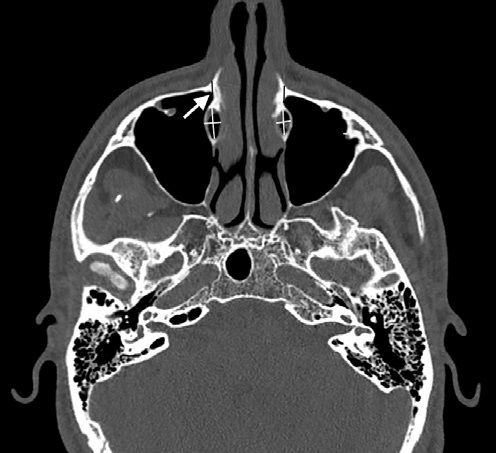

First, the images were adjusted to ensure a parallel Frankfort horizontal plane in order to obtain a standardized head position. The frontozygomatic sutures were used as a reference for the frontal view, and the orbital inferior margin and Porion landmark for the lateral view. The orbital floors were then aligned. The measurements were made from the location of the lacrimomaxillary suture, which was used as the reference for the midpoint measured when the axial section image showed the suture in linear format. The thickness of the maxillary bone adjacent to the nasolacrimal duct and the largest diameters of the nasolacrimal duct were then measured at this point and 2 mm above and below it. The lateromedial and anteroposterior diameters of the nasolacrimal duct were also measured (Figure 1). For intraobserver reproducibility, 25% of the sample was re-evaluated after 30 days.

Figure 1 Axial slice showing the lacrimomaxillary suture (white arrow) and the measurements of the nasolacrimal duct diameters (white line), as well as the thickness of the maxillary bone (black line)